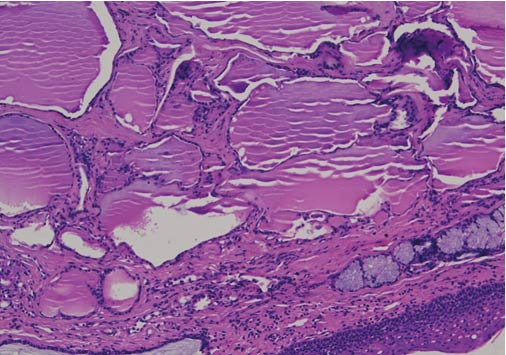

Microscopic description of the resected mass: Sections show stratified squamous epithelial lining. The subepithelial stroma shows islands of normal thyroid follicles and a few seromucinous salivary glands, with mild lymphoid cell infiltrate. There was no evidence of malignancy. (Figure 3 and 4)

Figure 3. Photomicrograph of Histology Section, Hematoxylin Eosin Stain, 10 X Magnifications, Showing Covering of Normal Squamous Epithelium of Tongue, With Many Variable Sized Colloid Filled Thyroid Follicles in the Subepethelium

Conclusion: Excised swelling base of tongue - LINGUAL THYROID.